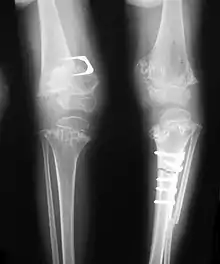

| Pseudoachondroplasia. Shoulders and Humeri. Note the dysplastic proximal humeral epiphyses, metaphyseal broadening, irregularity and metaphyseal line of ossification. These changes are collectively known as "rachitic-like changes". Lesions are bilateral and symmetrical. | |

Skeletal radiography

Accurate assessment of plain radiographic findings remains an important contributor to diagnosis of pseudoachondroplasia. It is noteworthy that vertebral radiographic abnormalities tend to resolve over time. Epiphyseal abnormalities tend to run a progressive course. Patients usually suffer early-onset arthritis of hips and knees. Many unique skeletal radiographic abnormalities of patients with pseudoachondroplasia have been reported in the literature.[2][7][4]

- Together with rhizomelic limb shortening, the presence of epiphyseal-metaphyseal changes of the long bones is a distinctive radiologic feature of pseudoachondroplasia.

- Hypoplastic capital femoral epiphyses, broad short femoral necks, coxa vara, horizontality of acetabular roof and delayed eruption of secondary ossification center of os pubis and greater trochanter.

- Dysplastic/hypoplastic epiphyses especially of shoulders and around the knees.

- Metaphyseal broadening, irregularity and metaphyseal line of ossification. These abnormalities that are typically encountered in proximal humerus and around the knees are collectively known as “rachitic-like changes”.

- Radiographic lesions of the appendicular skeleton are typically bilateral and symmetric.